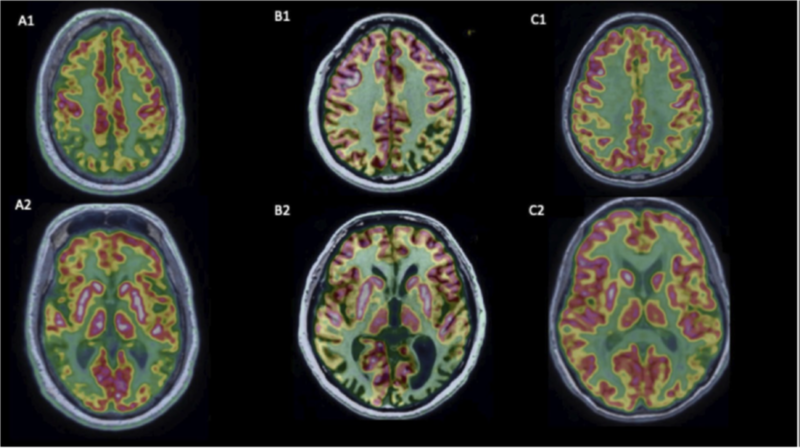

Various PET ligands have been used to differentiate between different aetiologies of dementia. FDG-PET is used to characterise regions of hypometabolism seen in different forms of dementia. In AD, hypometabolism is typically seen in bilateral medial temporal and parietal regions, including precuneus.

The pattern of hypometabolism also differs between the various subtypes of AD. Areas of affection in the other types of dementia are summarised in the table below:

FDG-PET features of AD and its variants: A)Typical AD, B) Posterior Cortical Atrophy variant, C) Logopenic Variant of Primary Progressive Aphasia variant.